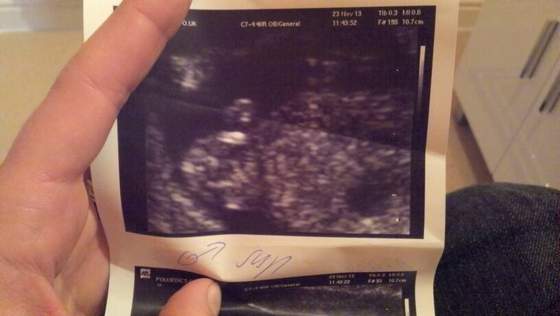

widac siusiaka ;))) miedzy udem a lydka